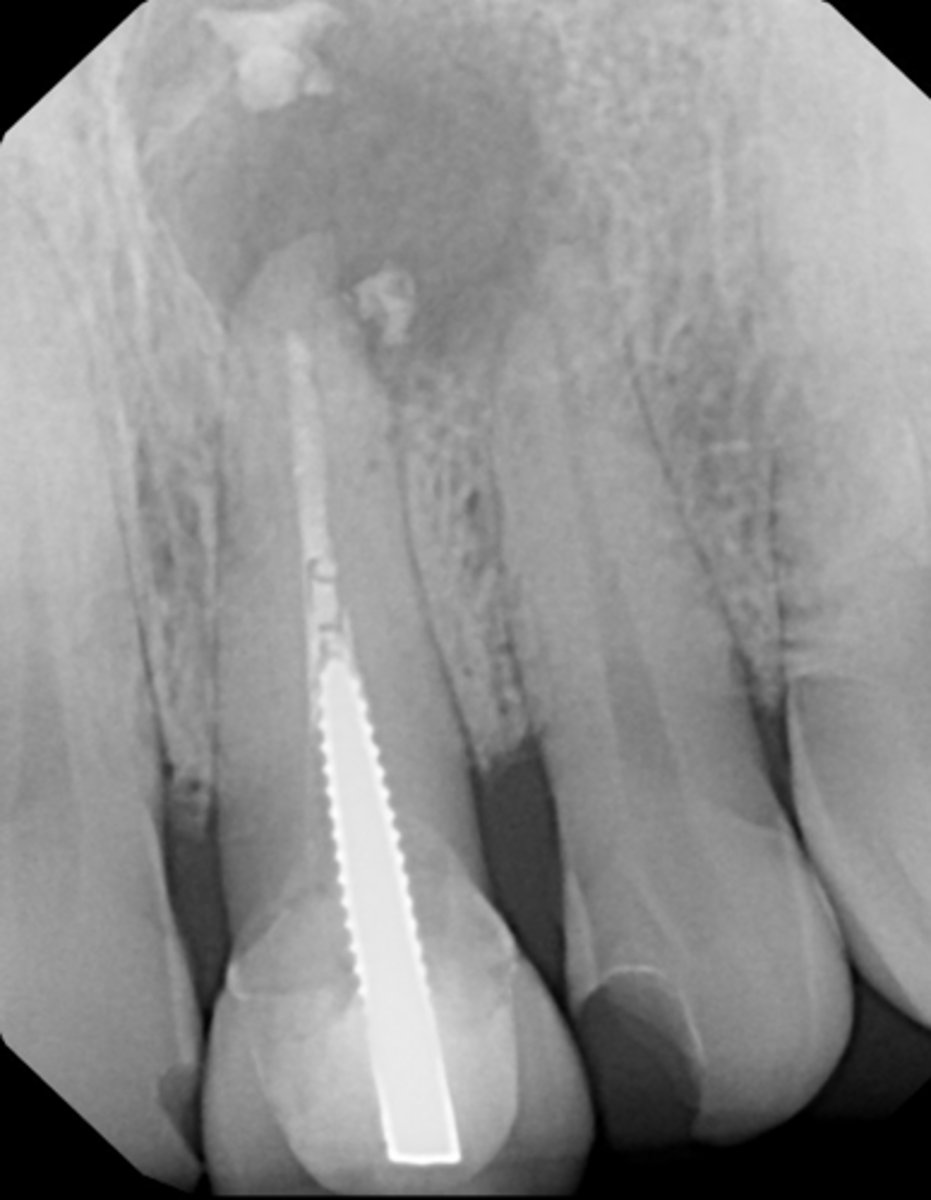

calcified/non-negotiable canal

What is the cause of this apical radiolucency?